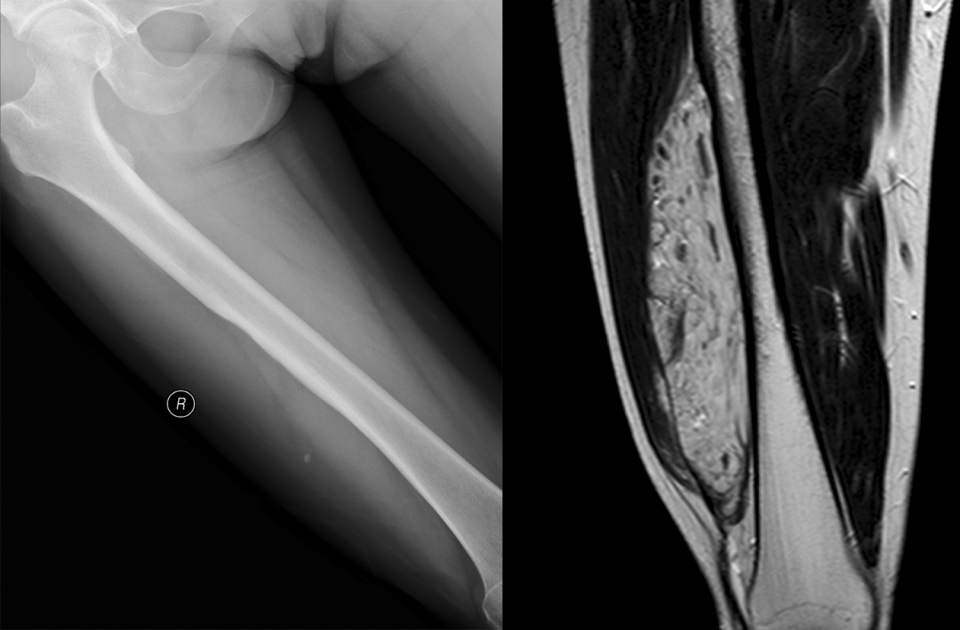

反应性骨膜增生

反应性骨增生是病变周围正常骨组织遭到肿瘤破坏后的反应骨,它并非骨肿瘤的特有征象,在骨创伤、骨感染时也可见到。良性肿瘤如骨样骨瘤、骨母细胞瘤等周围可见反应性骨增生(图 51、图 52)。原发于骨髓的恶性肿瘤如尤因肉瘤、骨淋巴瘤、骨恶性纤维组织细胞瘤等以及部分骨转移瘤均可在肿瘤周围产生大量反应性骨增生(图 53、图 54)。X 线平片或 CT 表现为松质骨内斑片状均匀骨化影或大量棉团样骨化影。亦有在多发灶性溶骨性破坏周围产生散在片状骨化影。

图片

图 51.反应性骨增生:骨样骨瘤

图 52.反应性骨增生:骨母细胞瘤骨

图 53.反应性骨增生:骨淋巴瘤

图 54.反应性骨增生:骨转移瘤